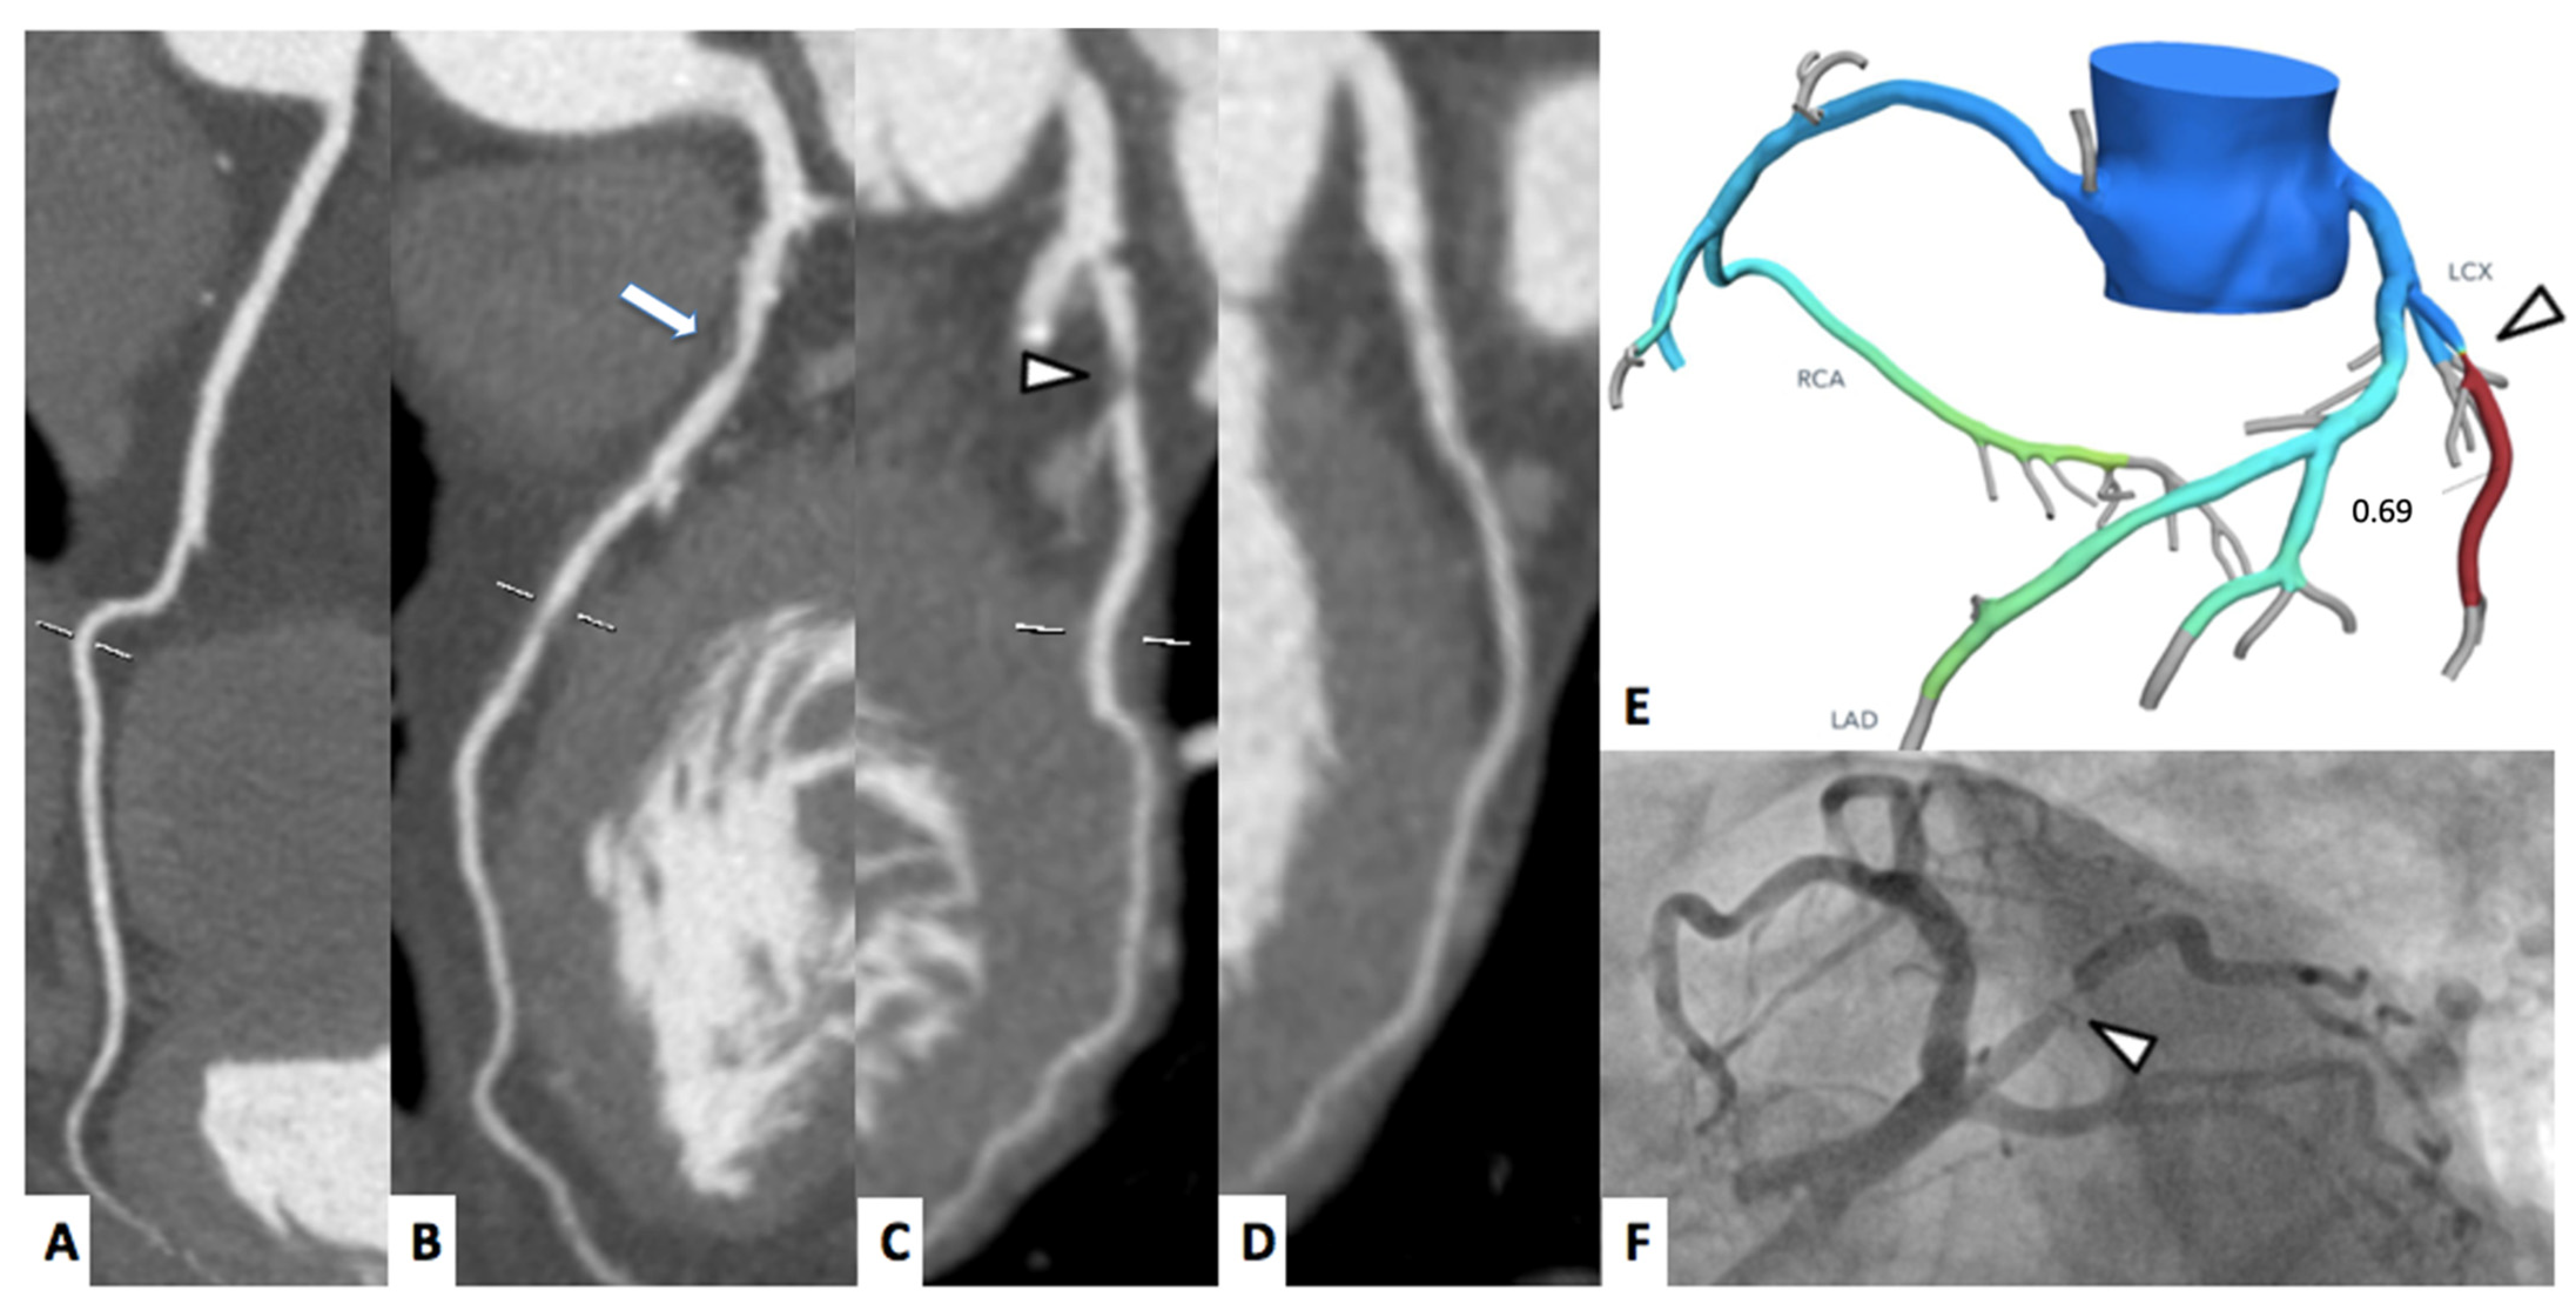

A representative case of FFRct and myocardial perfusion are shown in Figure 2 and Figure 3, respectively.

Figure 2.

A 70-year-old female patient underwent to CCTA for chest pain. Right coronary artery (A) and left circumflex artery (D) were free from significant stenosis; whereas left anterior descending artery shows moderate proximal stenosis ((B), arrow). Ramus intermedius shows a severe, fibro-lipid plaque stenosis ((C), arrowhead). The FFRCT assessment confirmed the functional significance of the stenosis proximal-ramus intermedius ((E), arrowhead), whereas the FFRCT values of the left anterior descending artery were above the ischemia threshold of 0.80. The invasive coronary angiogram ((F), arrowhead) shows severe stenosis of the proximal tract of the ramus intermedius.